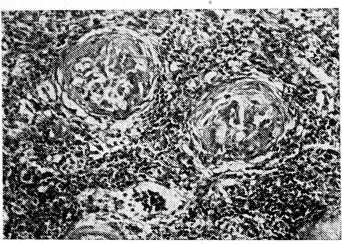

Анализ клинического течения болезни, результатов рентгенологического обследования и морфологического исследования почек больных пиелонефритом убедил нас в том, что ранее существовавшие представления о пиелонефрите как очаговом поражении всей паренхимы почки требуют сегодня пересмотра. Пиелонефрит может иметь строгую локализацию в одной из частей почки при сохраненной «'здоровой» остальной паренхиме. Об этом свидетельствуют данные сравнительного морфологического исследования ткани резецированной и «здоровой» части почки, полученной при операциях по поводу локального пиелонефрита (рис. 1).

Рис. 1. Ткань резецированного нижнего полюса почки больной Л. (Окраска гематоксилин-эозином,Х400.) Массивная лимфогистиоцитарная инфильтрация стромы, разрастание соединительной ткани, склероз клубочков. Сморщивание ткани.